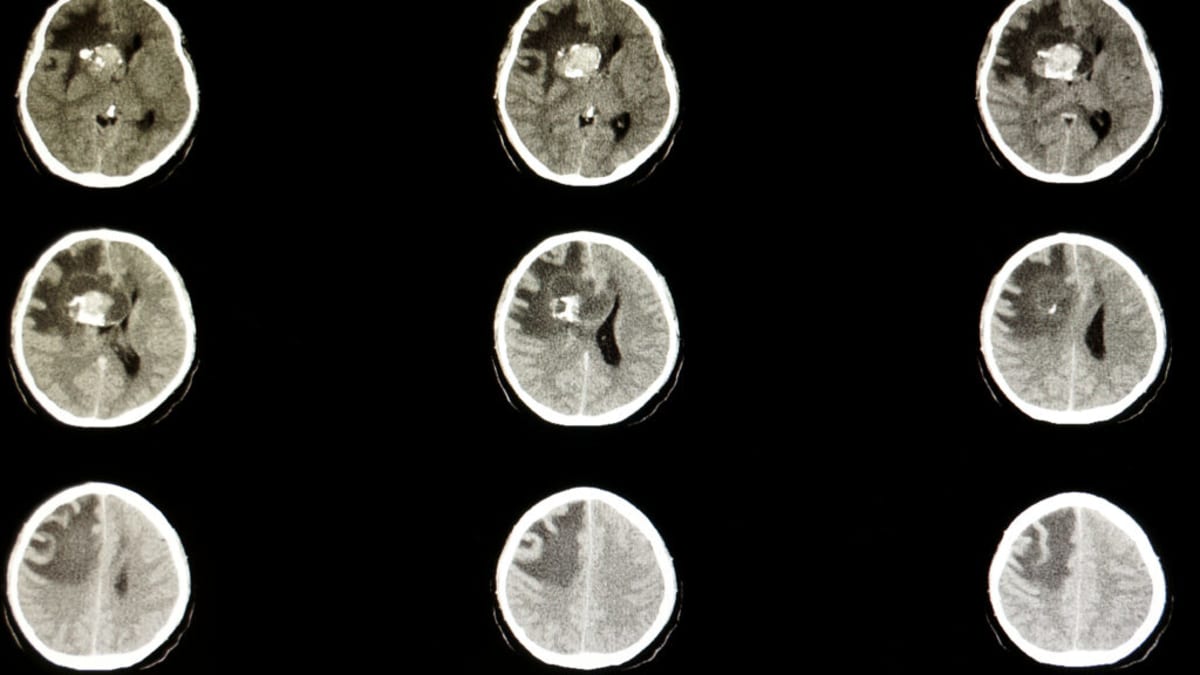

The Bay Area biotech company makes Ojemda, a drug approved in 2024 to treat pediatric low-grade glioma. This is the most common type of brain cancer in children.

Pediatric low-grade glioma affects thousands of children every year. Before Ojemda's approval, treatment options were limited and often came with harsh side effects that could impact a child's development.